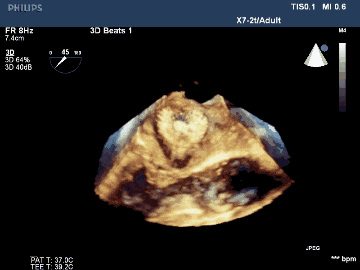

術(shù)后TEE三維重建影像示封堵器位置佳,封堵完全